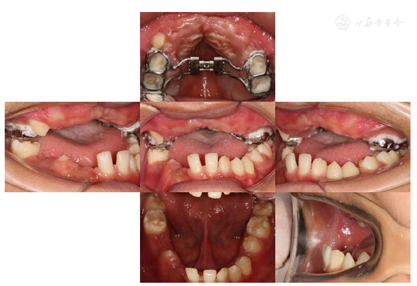

患者身高160cm,体重56kg,神志清,合作,智力正常。(1)口外检查:双肩陡峭下垂,肩关节活动度大,双肩可向前相互靠拢,两侧锁骨端缺如明显可见,手部可见远端指骨较短。头颅增大,面骨相对较小,眼距增宽,鼻梁塌陷;面型对称,颞下颌关节未见明显异常;面中份发育不足,III类骨性错

畸形(图1)。(2)口内检查:混合牙列,31、41、16、26、36、46萌出,37、47部分萌出,剩余乳牙滞留;54、64远中邻

面龋,探(-),叩(+),松0-I°,龈正常;全牙列反

,反覆盖10mm,双侧尖牙及磨牙近中关系;51、61扭转,上颌牙弓狭窄,腭盖高拱,31、41间可见间隙约5mm(图2)。(3)影像学检查:①曲面断层片示多数乳牙滞留,恒牙迟萌,多颗埋伏阻生多生牙。54、64远中邻面低密度影及髓,牙根吸收(图3);②CBCT示全口恒牙排列紊乱,上下颌骨内可见13颗多生牙,均位于恒牙胚舌腭侧,形态类似相邻恒牙胚(图4);③头颅侧位片示头颅侧位片示上颌骨发育不足(NA-Apo:-5.9°),下颌前突(SNB: 98.2°;FH-NPo:90.0°),骨性III类错